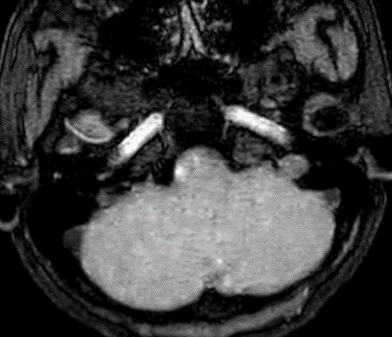

Các thăm dò hình ảnh khác như CT ngực, CT bụng và MRI sọ não không phát hiện tổn thương di căn.

Không phát hiện hình ảnh bất thường trên phim cộng hưởng từ sọ não